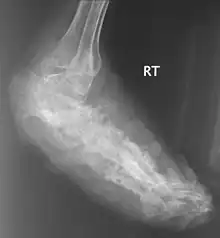

| An infected foot | |

X rays and ultrasonography may be carried out to assess the extent of the disease. X rays findings are extremely variable. The disease is most often observed at an advanced stage that exhibits extensive destruction of all bones of the foot. Rarely, a single lesion may be seen in the tibia where the picture is identical with chronic osteomyelitis. Cytology of fine needle aspirate or pus from the lesion, and tissue biopsy may be undertaken sometimes.[11] Some publications have claimed a "dot in a circle sign" as a characteristic MRI feature for this condition (this feature has also been described on ultrasound).[14]